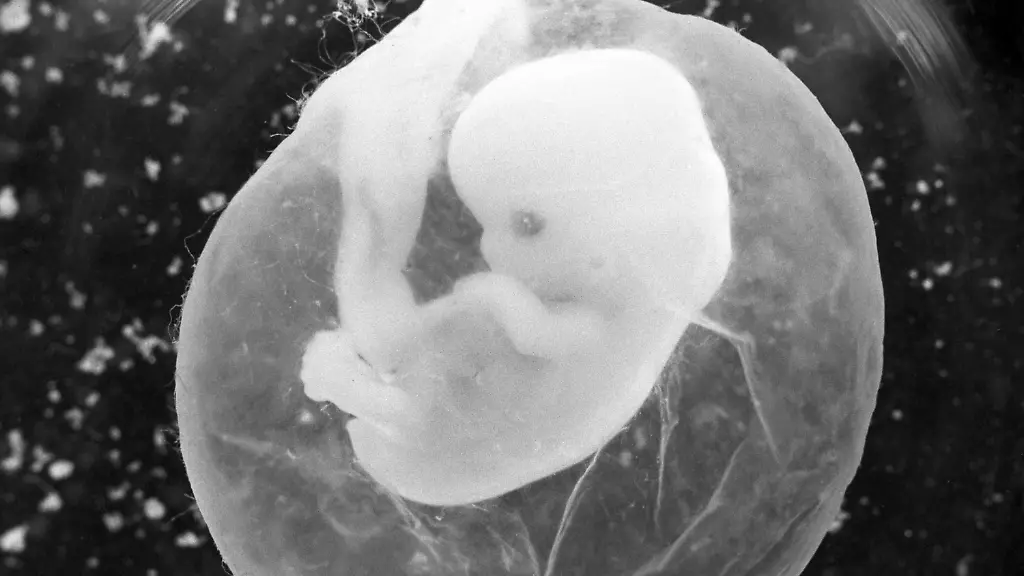

Infiziert sich eine werdende Mutter während der Schwangerschaft mit Toxoplasmose, kann das Kind in Gefahr sein.

(Foto: dpa)

Eine Infektion mit Toxoplasmose kann vor allem für Ungeborene gefährlich werden. In Deutschland wird die Erkrankung aber oft nicht diagnostiziert. Infizierte Neugeborene kommen dann mit Nervenschäden oder Augenproblemen auf die Welt.